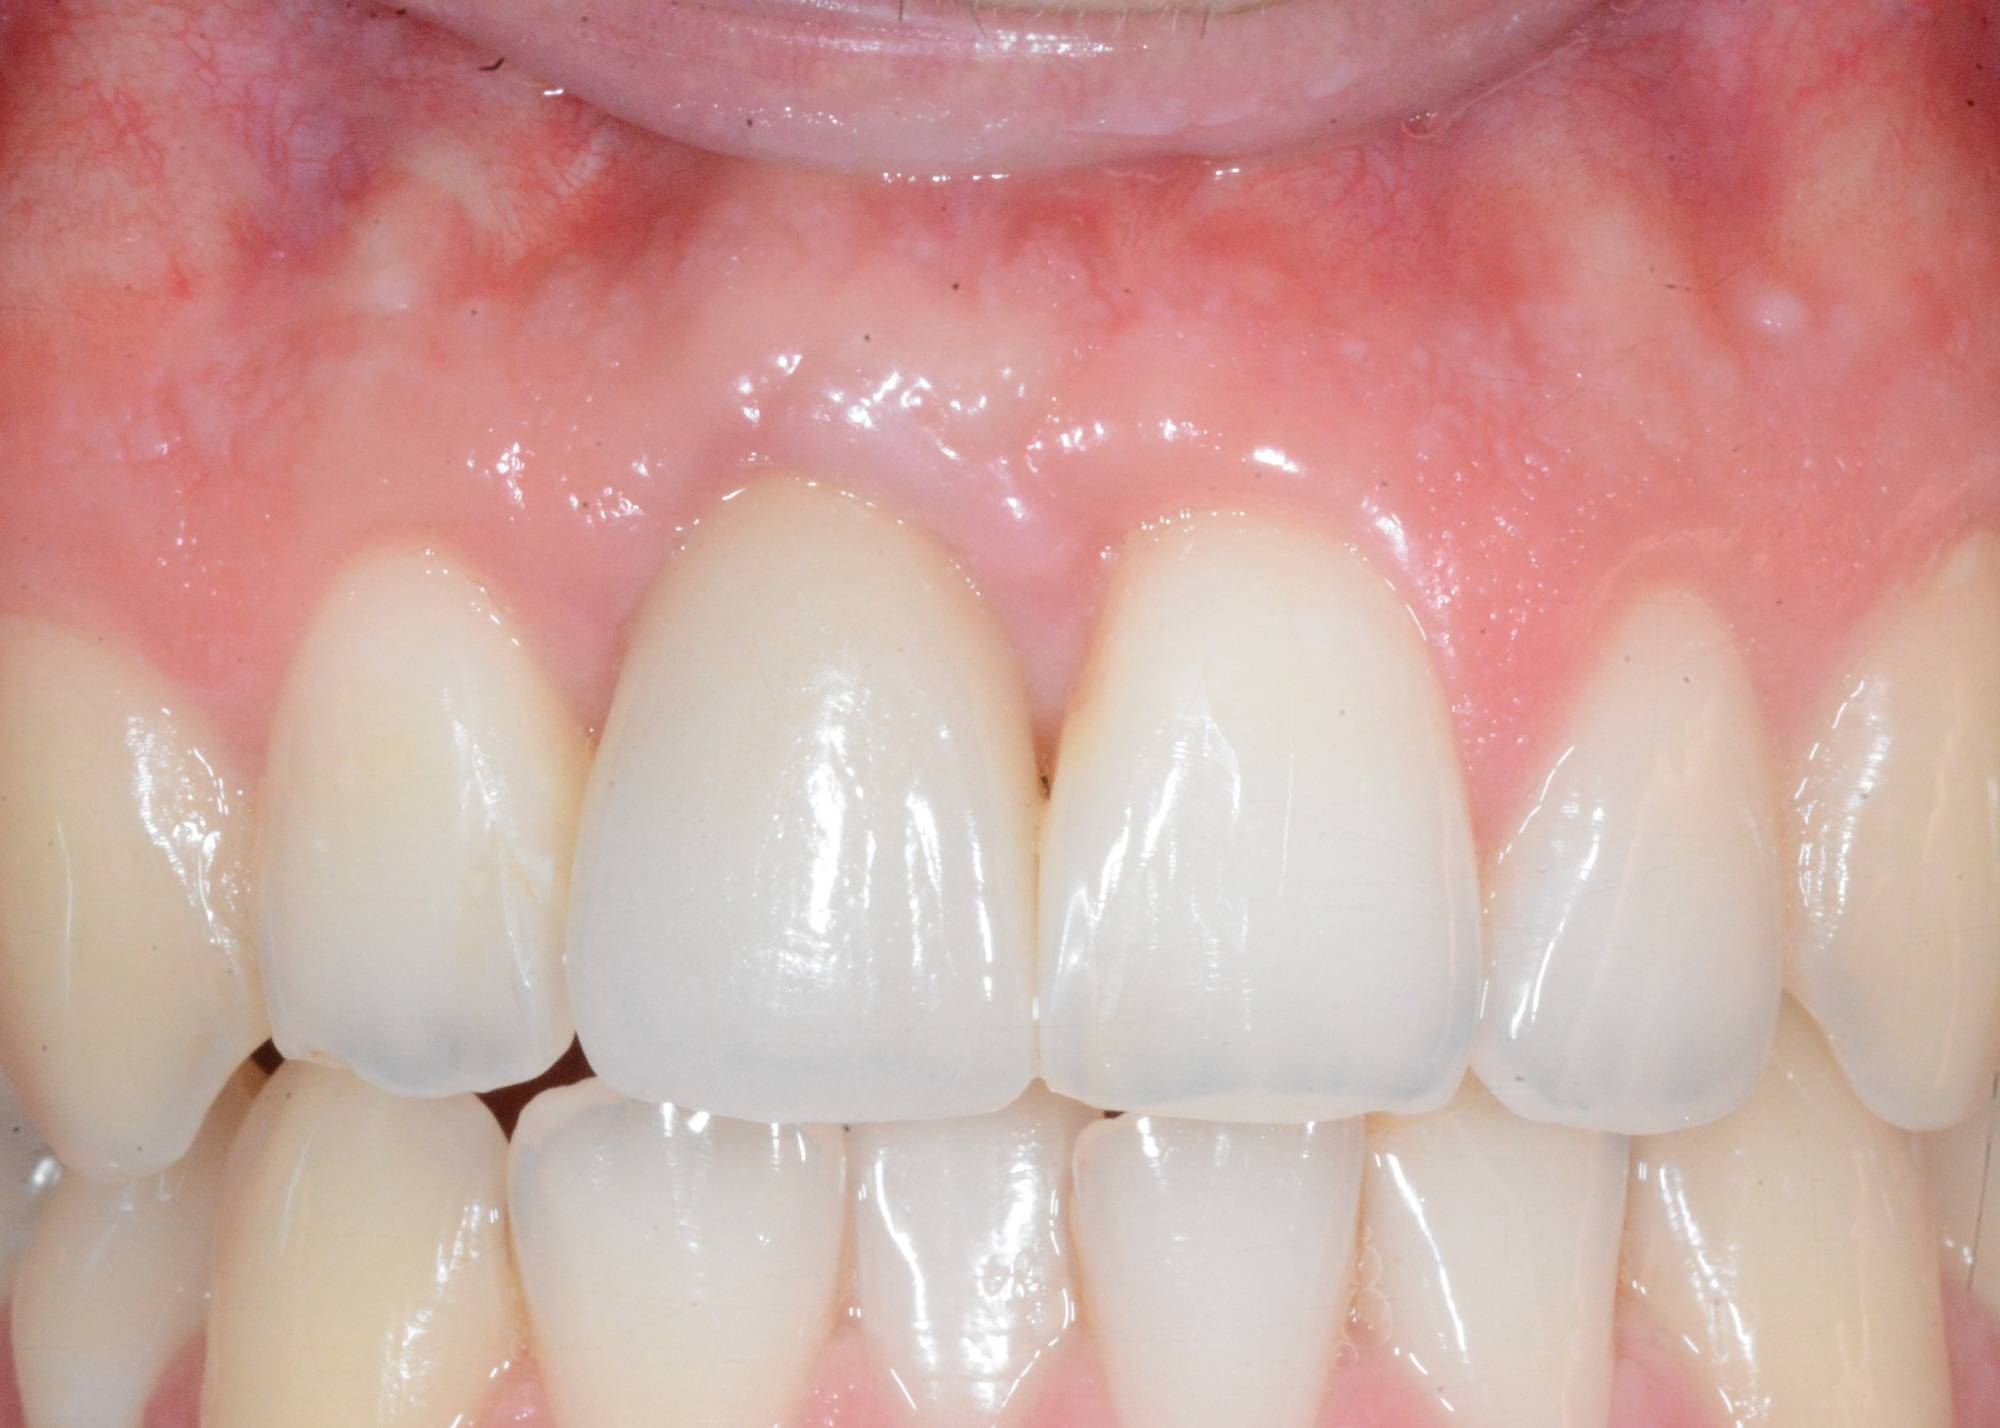

Indovina dov'è l'impianto, memory game

Ti sembra tutto normale in questa foto? Incisivi allineati e con un bel colore chiaro, gengive perfette e assolutamente non infiammate. E se invece ti dicessi che uno di questi denti è un impianto? Su quale scommetteresti? Ti sei mai fatto dei problemi a scoprire i denti quando ridi? Alle volte una caduta accidentale o un trauma durante un’attività sportiva possono toglierti la voglia di ridere liberamente. Guarda la foto successiva e capirai. A questo punto cosa potrebbe capitare? Inizi a sorridere con le labbra sigillate perché ti vergogni del tuo “buco” mentre ridi e ti diverti in compagnia. Questo giovane ragazzo ha perso l’incisivo centrale durante una partita di calcio fra amici. Aveva addirittura perso la parte esterna dell’osso che lo teneva in posizione. Ho dovuto mettergli un impianto osteointegrato e fare quello che noi dentisti chiamiamo “rigenerazione ossea guidata” per ricostruirgli l’estetica naturale che vedi nella prima foto. Solo nella terza puoi vedere cosa c’è dentro, al posto del suo dente ormai perso. La cosa bella è che non è mai stato senza il suo dente, nemmeno per un giorno. Premesso che è sempre meglio curare e salvare i propri denti, quando li devo sostituire, puoi contare sull’efficacia e sull’aspetto naturale degli impianti dentali. Questo ed altro è quello che facciamo nello Studio dentistico del dott. Fabio Ballestrasse a Besana Brianza (MB) e se sei di Verano Brianza, puoi raggiungerci facilmente.